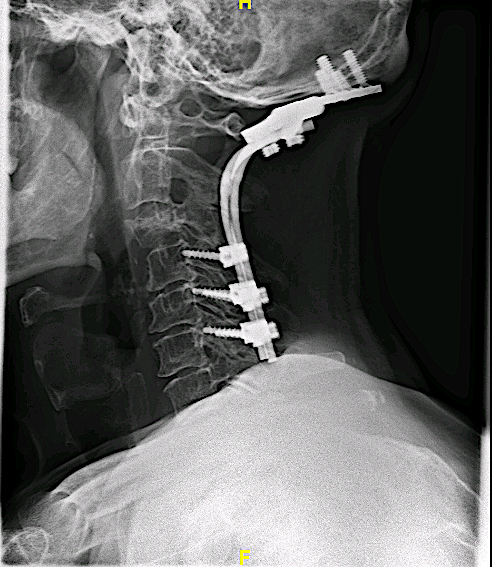

La resonancia postoperatoria demostró una adecuada descompresión. El paciente fue derivado para tto oncológico de rescate. La evolución postoperatoria fue favorable desde el punto de vista neurológico, con recuperación progresiva de la focalidad hasta autonomía completa.

RM 6 meses postor

Control 1 año